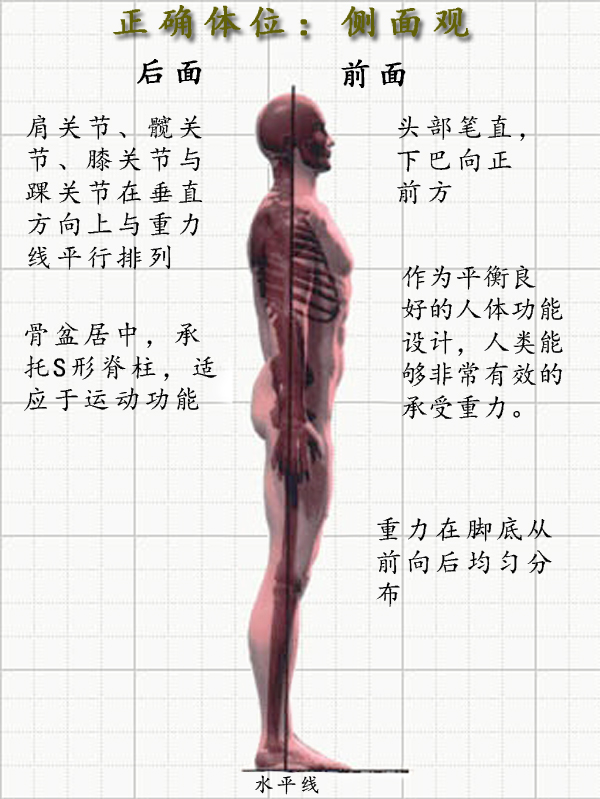

体态分三个面去看,正面,侧面,背面。这里我们先说侧面。体态的问题就是在颈椎,胸椎,腰椎三个曲度发生了的不同组合式 变化 ,让你看上不那么顺畅好看了,甚至让你 身体疼痛 。

中立位

我们这里先说侧面看的体态中立位。如下图,如果我从天花板挂一个铅垂线,让线穿过你的脚一侧的外踝,体态好的人,线会穿过你的膝盖前 1 / 3 处,骨盆大转子,肩峰和耳垂。如果有任何的偏离,都基本说明体态出现了问题。

答案是有的,但我们所有人都不完美。对于大多数人来说, 良好的体态要求身体的各 部位 保持在正确的位置上,而不良体态往往可能导致 肌肉疼痛 , 关节活动 障碍,或是全身不适。传统意义上来讲,物 理疗 法、整骨、脊椎推拿疗法和目前的 瑜伽理疗 师,评估体态时,都是通过将 患者 的体态与正直的骨架进行比较而得。通过从背面、侧面、正面,观察客户身体各个部位如何有机结合,再与无性别的骨架的各部位结合状态作比较,得出结果。毫无意外,你会发现我们许多人的体态与 标准 骨架所展示的体态有很大的 区别 。

通过侧面观察,我们能发现自己在矢状面(前后) 的体态问题。正常状态下,人类 的身体中这五个点应该近似位于一条直线的:耳垂、肩峰、股骨大转子、股骨外髁、外踝。

由于人类的大量运动是在矢状面进行的,因此从侧面观最容易发现体态问题,所以我们一般会以侧面观察作为体态评估的开始 。人体的五个主要关节在矢状面的功能紊乱会导致一系列的代偿现象,常见的矢状面体态问题包括骨盆前倾、骨盆后倾、圆肩探头、驼背等。